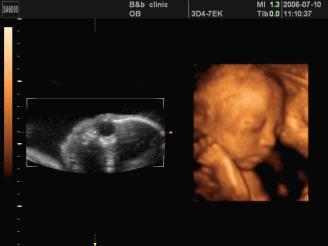

超声检查是评估胎儿生长发育情况,筛查胎儿畸形的首选检查方法,其优势及其在产科中的作用是其他影像技术所不能替代的!

超声可以评价胎儿生长发育、胎盘羊水等附属物情况、检测胎儿结构畸形(功能、代谢、精神、行为等方面的出生缺陷,超声不能检出)、筛查胎儿染色体异常高危人群、发现某些阳性特征而向临床提出进一步的检查要求或者某种疾病的一些线索。

目的:此期主要进行遗传学超声检查以筛查胎儿染色体异常高危人群,重点测量胎儿颈项部透明层(NT)、鼻骨等;同时可检出一些大体结构畸形,如无脑儿、连体双胎等。

目的:此期胎儿各器官基本发育,羊水量适中,超声图像清晰,是胎儿畸形筛查最佳时间,大部分胎儿结构异常可在这个阶段检出。